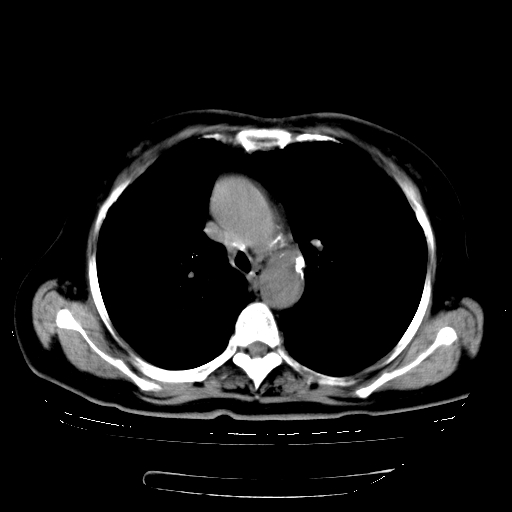

女,70岁,咳嗽、咳痰一个月,低热一周。

一元论:内膜结核伴下肺阻塞性肺炎并双肺播散!另:主动脉夹层。右侧少量胸腔积液。

支持,首先一元论解释。胸主动脉部分层面环形低密度,中心强化。环形影不强化。不象真假腔的改变。我考虑动脉炎,不太支持夹层动脉瘤-和大家的观点不一致,希望楼主让患者再做个心血管的彩超吧。